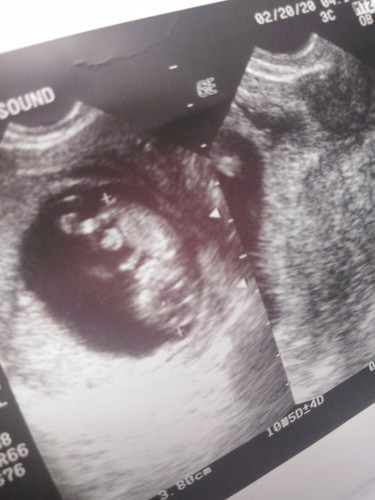

Retrochorionic Hemorrage

Good morning momsh. 11 weeks pregnant at 1st baby ko po. Nagpatransvaginal ultrasound po tulad ng sabi ni ob but to find out yung result meron 11 cc na dugo. Pero never po ako nagbleed. Malakas daw po si baby sabi naman ni doc lumalaban. Ngayon bed rest and duphaston 3x a day ang binigay ni ob. Nagwoworry lang po kasi ako ng sobra kasi baka alam nyo na, wag naman sana?. Any other suggestion po sana in regards sa gantong case? Salamat